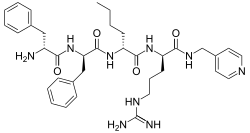

Opioid peptides

DAMGO DAMGO |

- DALDA (Tyr-D-Arg-Phe-Lys-NH2)

DALDA DALDA |